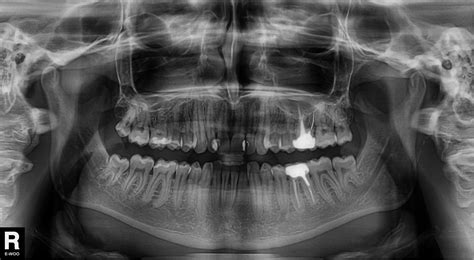

Maži vaikai dažnai praryja smulkius objektus. Žinant ar tariant, kad vaikas prarijo pavojingą objektą, galintį sukelti virškinimo trakto obstrukciją ar perforaciją, būtina nedelsiant atlikti tyrimus. Pavojingais laikomi aštrūs svetimkūniai, didesni nei 6 cm ilgio ar 2 cm skersmens objektai, maitinimo elementai ir keli magnetai.

Literatūroje aprašyta atvejų, kai prarijusius magnetus vaikams išsivystė žarnų užsisukimas ir perforacija.